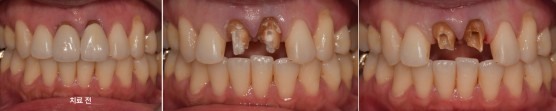

재신경치료 후 보철 치료

치료 기간 24. 03. 02 (당일 치료)

c.c 앞니 씌운게 오래되어서 새로해야하는지 상담 문의함

#11,21 뿌리 끝에 염증있어서 re-endo후 post cr설명 드리고 진행함.

치료 전

치료 후